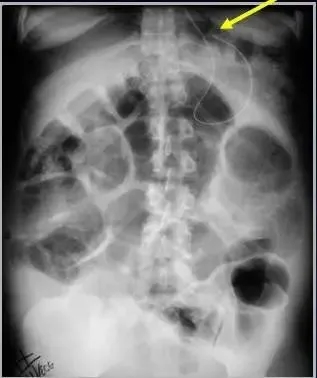

图:主动脉球囊反博置入,球囊近端(红箭)低于主动脉弓(绿箭)